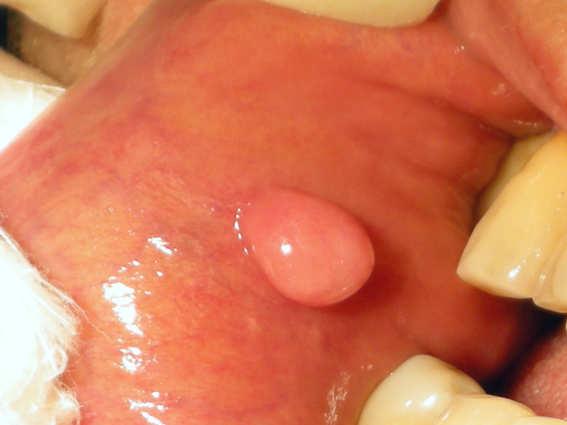

Morsicatio buccarum

Morsicatio buccarum (also known as "Chronic cheek biting," and "Chronic cheek chewing") is a cutaneous condition characterized by chronic irritation or injury to the buccal mucosa from repetitive chewing, biting or nibbling produces characteristic changes in the tissue.